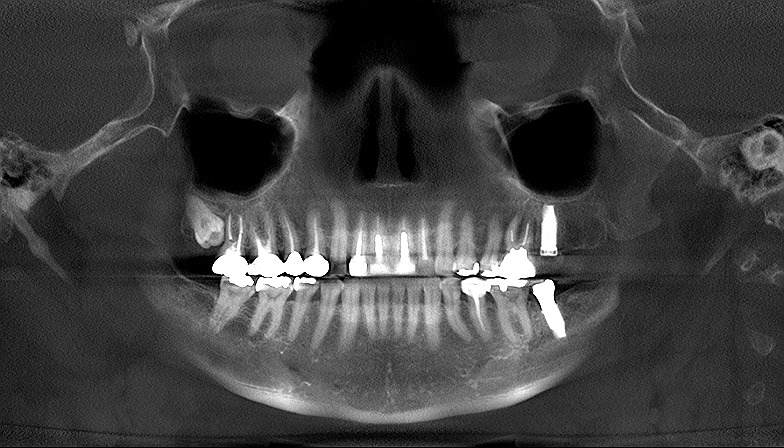

左上の最期臼歯のインプラント埋入から3か月 傷も癒えて上部構造を建てていきます|お知らせ |広島市安佐南区の歯科医院 左上の最期臼歯のインプラント埋入から3か月 傷も癒えて上部構造を建てていきます トップ お知らせ・ブログ お知らせ 左上の最期臼歯のインプラント埋入から3か月 傷も癒えて上部構造を建てていきます 左上の最期臼歯のインプラント埋入から3か月 傷も癒えて上部構造を建てていきます 傷も癒えました インプラントもマイナス値が出ました これより上部構造を作成していきます 印象時のデンタルレントゲンになります カスタムのチタン製のアバットメントになります 上部構造はセラミックにて仕上げていきます 術前のCTになります 術後のCTになります 術前のパノラマになります 術後のパノラマになります Web診療予約 初めての方へ 選ばれ続ける理由 院内設備について 歯が痛いしみる一般歯科 歯がぐらぐらする歯周病 健康な歯を保ちたい予防歯科 子供の虫歯予防をしたい小児歯科 銀歯をセラミックに審美歯科 白い歯を目指しませんか?ホワイトニング 矯正専門医がいるので安心矯正歯科 抜けた歯を補いたいインプラント・入れ歯 医院案内 スタッフ紹介 メリィハウス歯科クリニックオフィシャルホームページ ラベンダー歯科クリニックオフィシャルホームページ お知らせ・ブログ ホーム 診療科目 一般歯科 歯周病治療 予防治療 小児歯科 審美治療 ホワイトニング 矯正歯科 入れ歯・インプラント マウスピース矯正 初めての方へ 院長・スタッフ 設備紹介 医院案内・アクセス メニューを閉じる